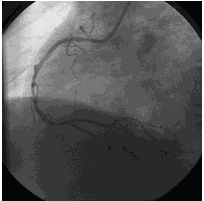

造影结果1:右冠弥漫性病变,近中段90%狭窄。

![]()

造影结果2: 左主干正常,前降支弥漫性斑块,近中段80%~90%狭窄,回旋支中远段80%~90%狭窄。

造影结论及应对策略:本病例行冠脉造影发现: 右冠弥漫性病变,近中段90%狭窄。左主干正常,前降支弥漫性斑块,近中段80%~90%狭窄,回旋支中远段80%~90%狭窄。家属要求PCI治疗。本次先开通右冠,择期开通左冠。